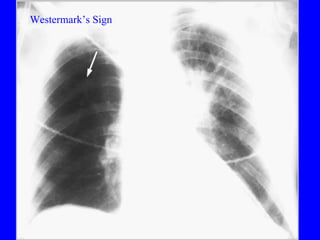

Diagnosis CXR Usually reveals a non specific abnormality.  14% normal Classic abnormalities include: Westermark’s Sign - focal oligemia Hampton’s Hump - wedge shaped density Enlarged Right Descending Pulmonary Artery (Palla’s sign)

PE Westermark’s Sign